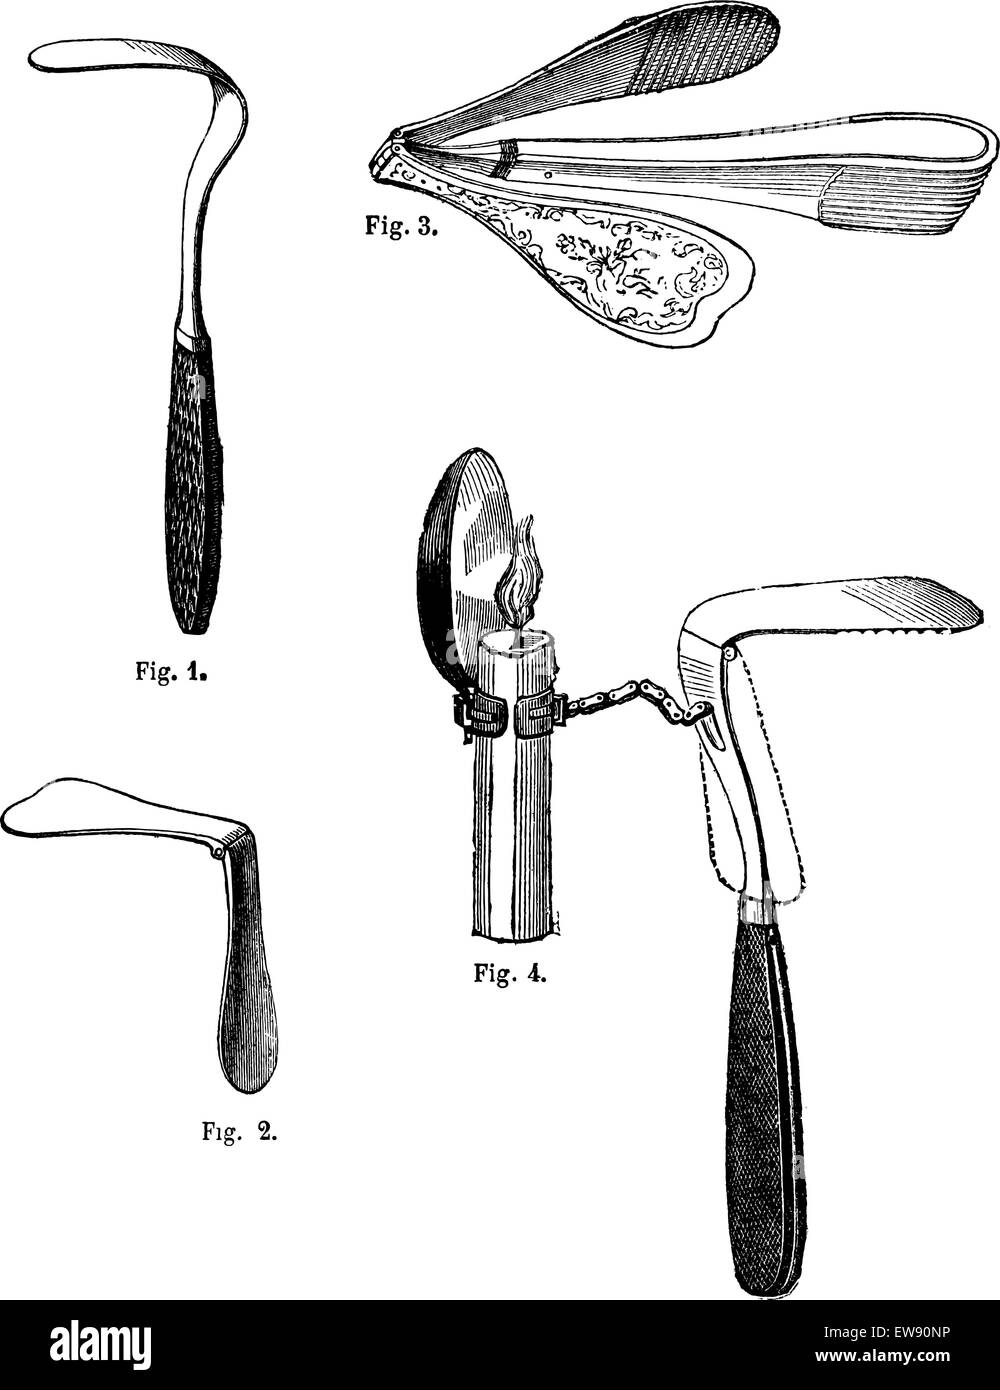

RFEW90NP–Fig 1. Abaisse-langue fixe, Fig.2 abaisse-langue articule, Fig 3. Abaisse-langue articulée, Ricord, Fig 4. Langue maternelle dep

RFEW9GN6–Fig 1. Abaisse-langue fixe, Fig.2 abaisse-langue articule, Fig 3. Abaisse-langue articulée, Ricord, Fig 4. Langue maternelle dep